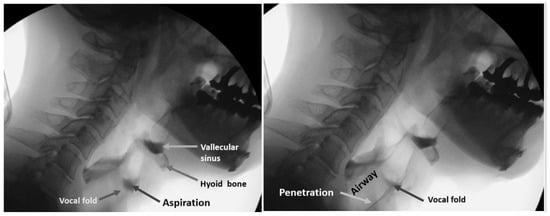

2.5. Classified Dysphagia (+) and Dysphagia (−) Groups

The protocol for the VF of each patient involved presentation of swallows with 1 to 3 mL standard meals with barium without any instruction for swallowing. All three or four dentists involved in the examination inspected laryngeal invasion, aspiration, and accumulation of epiglottis valley/pyriform sinus. At least two of the three or four observers were qualified as Board Certified Fellows of the Japanese Society of Dysphagia Rehabilitation. The examiners in the VF room can miss the findings on the monitor because they are concentrating on the patient’s condition. In our hospital, one or two dentists are in the VF room, and the others are outside the VF room, checking the monitor, to obtain consensus. Figure 8 shows the sample VF images of aspiration (left image) and penetration (right image).

Figure 8.

Sample VF images. Left image shows the aspiration and right image shows penetration.

Observers recorded these findings on the VF exam chart. These VF exam charts were used for the classification of a dysphagia (+) case and (−) case. In this study, penetration and aspiration cases were treated as a dysphagia (+) case.